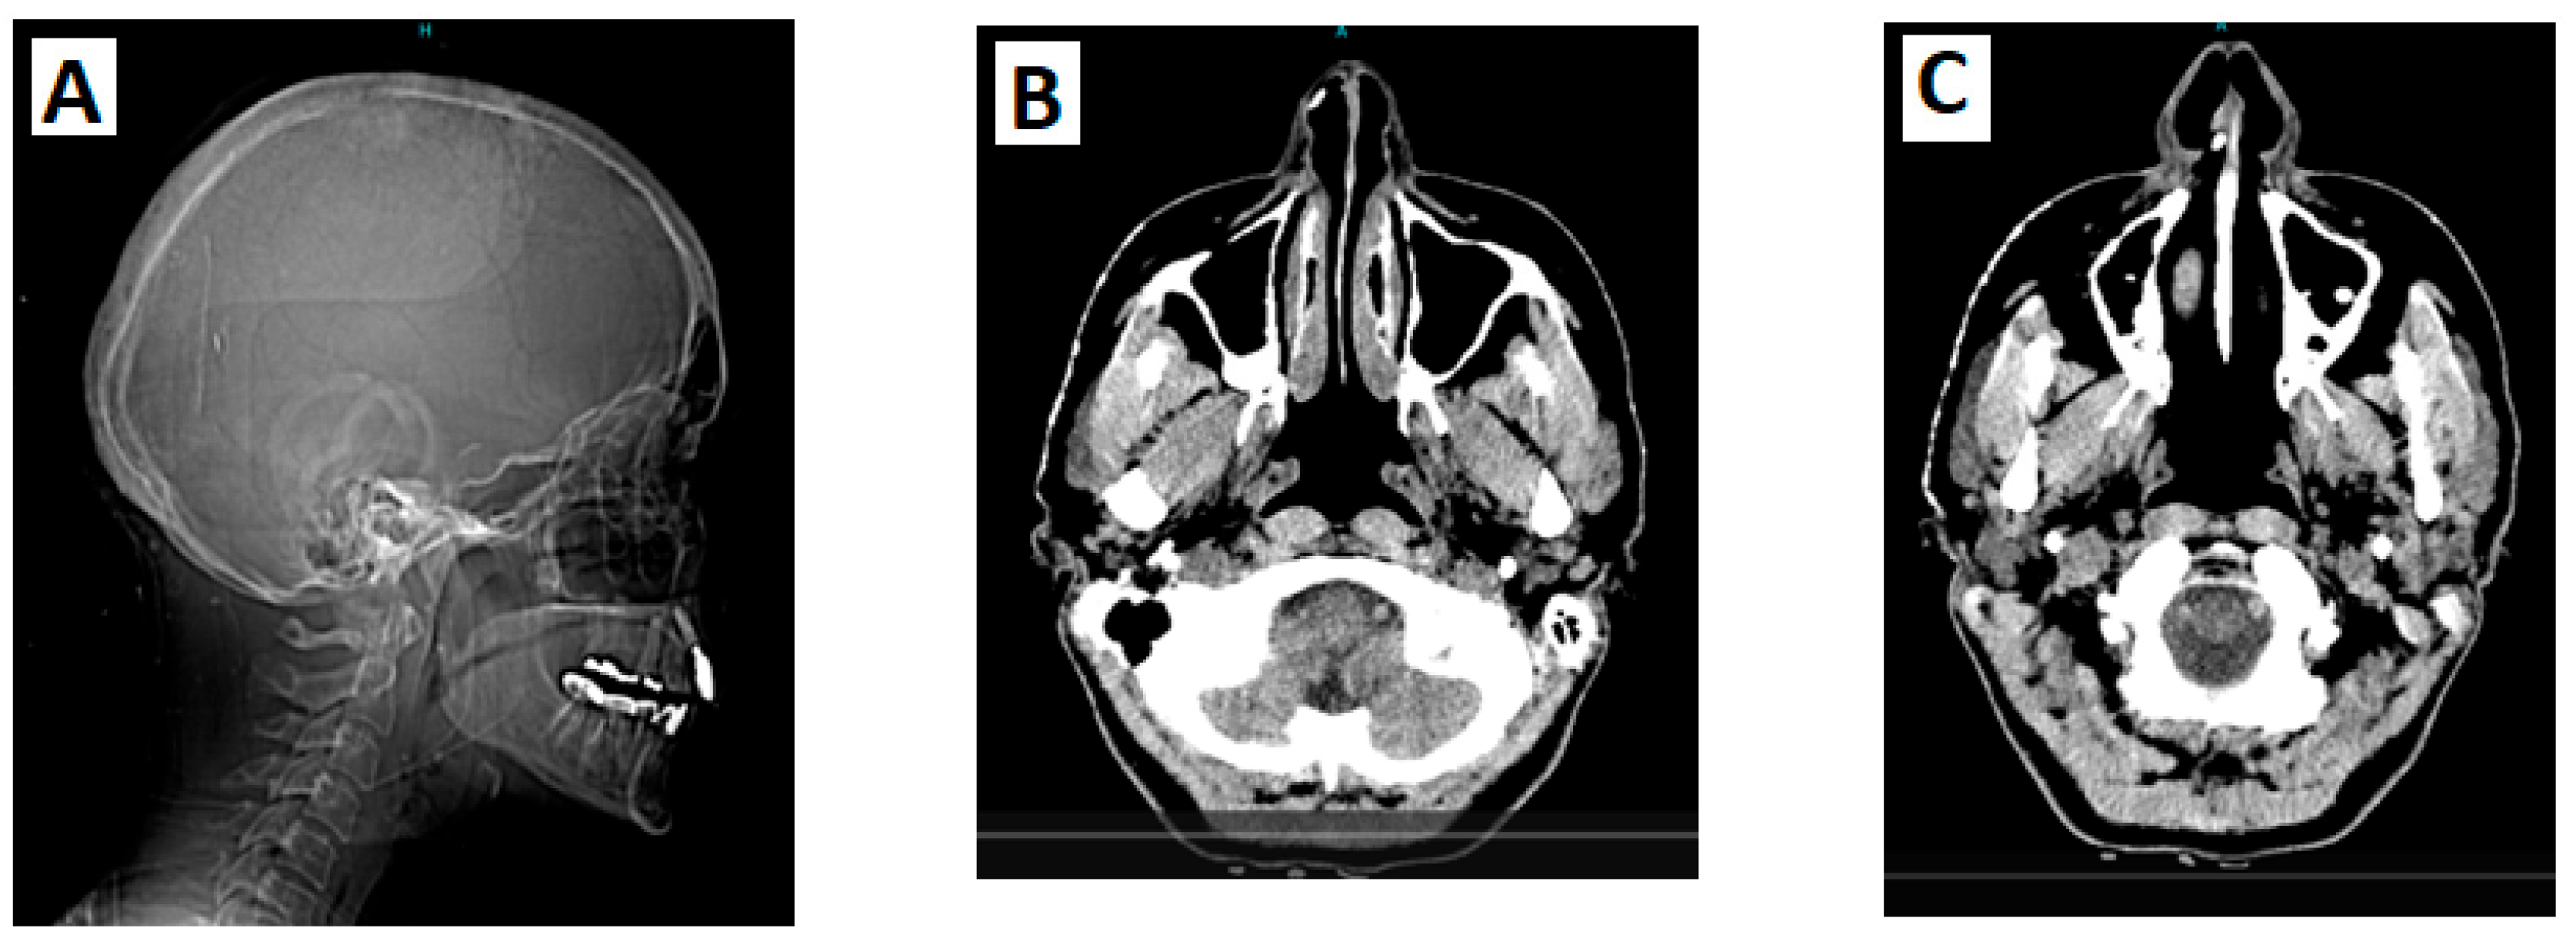

The patient first reported missing teeth (right side oligodontia) at the age of 8 years. At 18, she was diagnosed with hypothyroidism. A year later she noticed the development of hyperostosis and bony malformations on the right side of her face, including her nose, forehead, skull, and below the right eye (

Figure 3). The patient also underwent radiological investigations, including a computerized tomography scan of the skull, which showed a pedunculated exostosis/osteoma in the right frontal sinus, smooth hypertrophy of the right nasal bone with microcalcifications, focal calcifications in the right inferior nasal cavity, and microcalcifications in the right temporal and frontal subcutaneous tissues (

Figure 2). Brain imaging was normal.

Figure 2.

A: CT scan of the head and neck (sagittal plane) reveals a bony projection near the anterior border of the right maxillary sinus, whereas the inferior turbinate shows slight calcification/thickening; B: CT brain angiography shows a focal calcification in the lateral cartilaginous wall of the right inferior nasal cavity; C: CT brain angiography reveals an osteophytic spur at the anterior border of the right maxillary sinus that projects into the right nasal cavity.